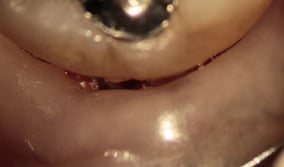

ポケット

肉眼では見えない奥歯の奥の歯と歯肉の境目(ポケット)も中の様子も拡大視野下では診ることが可能な場合があります。